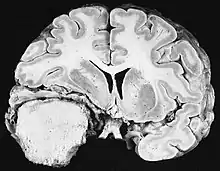

Une première subdivision des tumeurs du système nerveux central (SNC) se situe entre les tumeurs primaires (provenant directement du SNC) et métastatiques (provenant d'un autre organe). Ces derniers ont une incidence environ dix fois supérieure à celle des premiers. Les tumeurs cérébrales sont des néoplasmes qui se développent dans le cerveau. Les tumeurs telles que le méningiome, qui, en raison de leur masse comprimant mais ne pénétrant pas le cerveau, et les tumeurs hypophysaires et épiphysaires, qui sont situées sur le tronc cérébral, sont souvent appelées à tort tumeurs cérébrales. Le terme de tumeurs intracrâniennes les résume plus précisément.

Les tumeurs primaires du SNC comprennent une variété d'entités pathologiques, chacune avec sa propre histoire naturelle. Du fait que les tumeurs gliales représentent à elles seules près de 40 % de ces tumeurs, on peut d'abord distinguer les tumeurs gliales (gliomes) des tumeurs non gliales. Les gliomes les plus courants sont les astrocytomes (provenant des cellules astrocytaires gliales), les oligodendrogliomes (provenant des cellules oligodendrogliales) et les épendymomes (provenant des cellules épendymaires).

Les tumeurs primitives malignes du système nerveux central sont relativement rares et représentent environ 2 % de toutes les tumeurs malignes. Les maladies tumorales du système nerveux central sont distribuées à 95 % sur le cerveau et à 5 % sur les méninges, les nerfs crâniens et la moelle épinière. Ils peuvent survenir à tout âge et le risque de développer la maladie augmente avec l'âge. Chez l'adulte, les gliomes peuvent être retrouvés histologiquement à partir du tissu de soutien des cellules nerveuses, dont environ 75 % de glioblastomes Astrocytomes IV. degrés avec un pronostic défavorable. Les tumeurs embryonnaires prédominent chez les nourrissons et les jeunes enfants. En Allemagne, environ 3 970 personnes sont tombées malades en 2 016 hommes et 3 460 femmes atteintes de tumeurs malignes du système nerveux central. En moyenne, les taux de survie sont de 21 % pour les hommes et 24 % pour les femmes. Les statistiques incluent également rarement les tumeurs histologiquement bénignes du SNC, qui surviennent dans environ 6 000 nouveaux cas par mensonge de l'année. Environ 65 % provient des méninges. Les femmes sont beaucoup plus touchées. Si elles ne sont pas traitées par chirurgie ou radiothérapie, même les tumeurs bénignes peuvent être mortelles en raison de la croissance progressive dans l'espace crânien fermé. La tumeur maligne intracrânienne du SNC la plus fréquente est le glioblastome, la plus bénigne étant le méningiome.

Glioblastome

Les tumeurs des cellules gliales les plus courantes et les plus malignes sont les glioblastomes. Ils consistent en une masse hétérogène de cellules d'astrocytome peu différenciées principalement chez l'adulte. Ils surviennent généralement dans les hémisphères cérébraux, plus rarement dans le tronc cérébral ou la moelle épinière. Sauf dans de très rares cas, comme toutes les tumeurs cérébrales, elles ne s'étendent pas au-delà des structures du système nerveux central.

Le glioblastome peut provenir d'une forme diffuse (II. grade) ou un astrocytome anaplasique (III. grade) développer. Dans ce dernier cas, il est dit secondaire. Cependant, lorsqu'elle survient sans antécédent ni signe de malignité antérieure, on parle de maladie primaire. Les glioblastomes sont traités par chirurgie, radiothérapie et chimiothérapie. Ils sont difficiles à guérir et rares sont les cas qui survivent au-delà de trois ans.